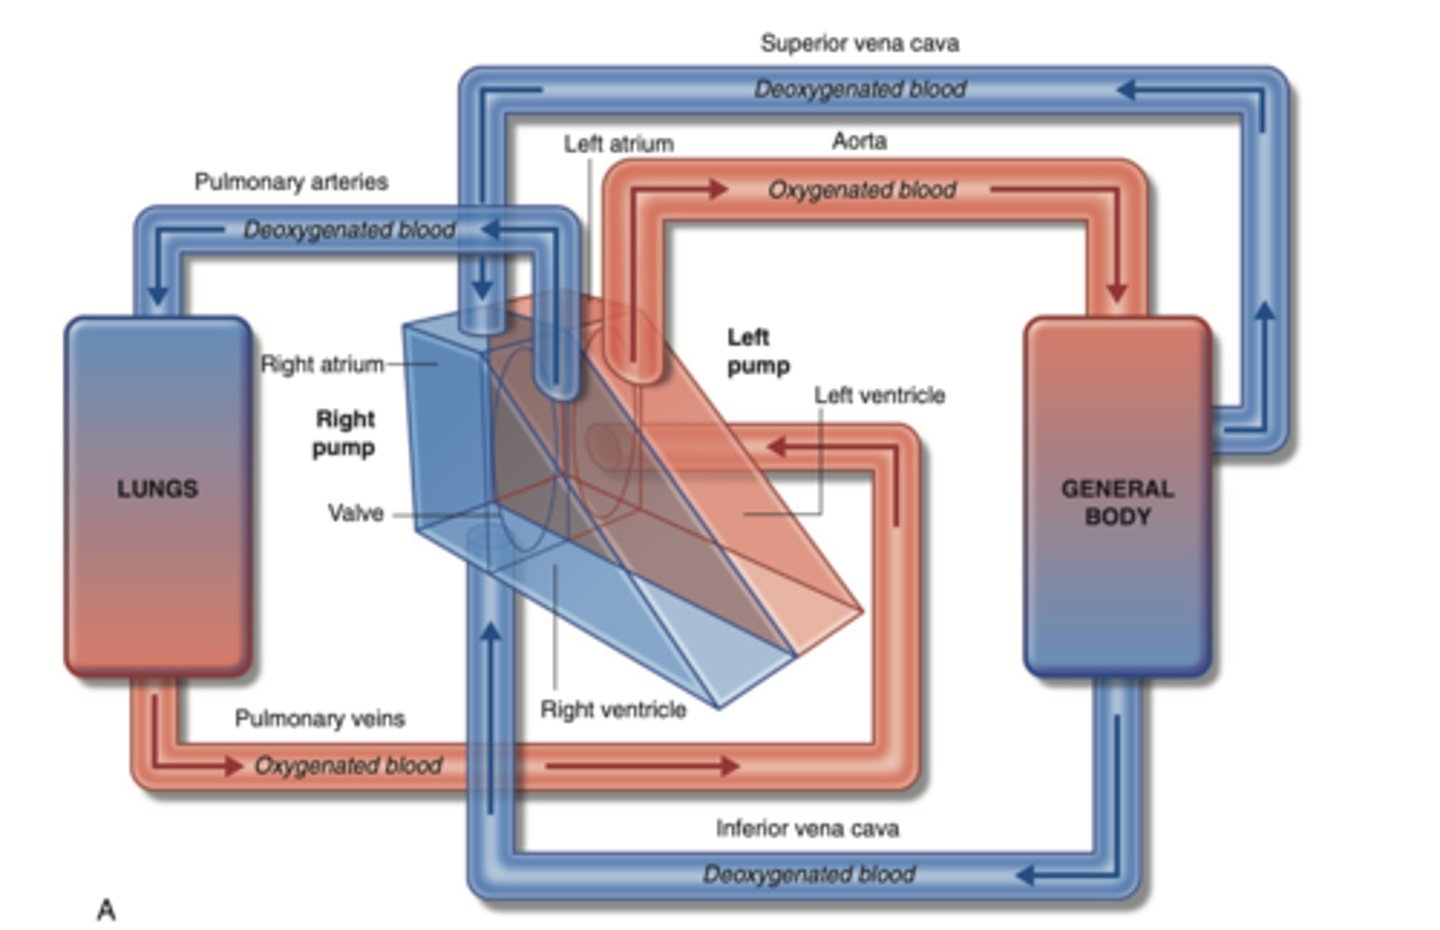

SYSTEMIC CIRCULATION

flow of blood from body tissue to the heart and then from the heart back to body tissues

It carries oxygen and nutrients to the cells and picks up carbon dioxide and waste products

Describe in detail systemic circulation

From the left ventricle, oxygenated blood,

through the arteries,

to the capillaries in the tissues of the body.

From the tissue capillaries, the deoxygenated blood

returns through a system of veins to the right atrium of the heart. (superior and inferior cava veins)

PULMONARY CIRCULATION

Circulation of blood between the heart and the lungs

transports oxygen-poor blood from the right ventricle to the lungs,

where blood picks up a new oxygenated blood

Describe in detail pulmonary circulation

From the right ventricle poor oxygenated blood is impulsed

to the lungs, through the pulmonary artery

blood is oxygenated

returns to the left atria through the pulmonary veins

from where is the right atrium receiving the blood?

From the whole body

Right ventricle pumps blood to?

pulmonary artery

from where receives blood the left atrium?

pulmonary veins

Where pumps blood the left ventricle?

into the aorta